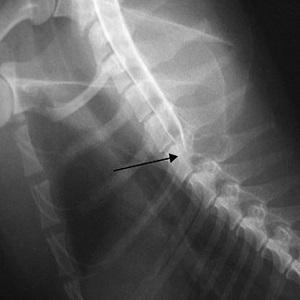

Из-за своей хрупкости ости подвержены переломам: они могут быть изолированными со смещением или без, а также совмещенными с другими переломами. Перелом представляет собой отрыв костного фрагмента от позвонка.

Причиной перелома становится не только прямой удар во время занятий спортом или ДТП, но и чрезмерное сгибание и разгибание шеи.

Например, резкие движения при копании земли лопатой, во время которых позвоночник постоянно сгибается и разгибается, могут стать причиной перелома остистого отростка. Пока позвоночник согнут, на него оказывается дополнительная нагрузка.